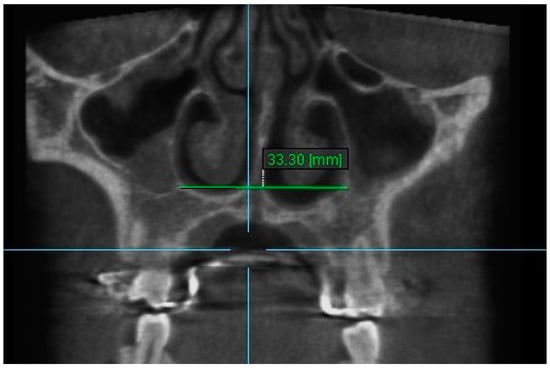

2. Nasal Width 2: The maximum lateral interior width of nasal cavity on coronal slice through the center of the root of the second premolar (Figure 4).

Figure 4.

Nasal Width 2.

8. Nasal Floor 8: The distance between the junction of anatomical floor of nasal cavity and the medial aspect of the floor ipsilateral sinus on coronal slice through the center of root of the second premolar (Figure 10).

Figure 10.

Nasal Floor 8.

In the current study, a statistically significant increase was found in all measurements of the nasal width, nasal floor and the aperture of the midpalatal suture immediately after RPE expansion (T2–T1) (Table 2). Previous studies evaluating nasal changes after RPE showed similar results to our study [4,35,40,44,47,48]. Fastuca et al. [48] found that there was no statistically significant difference between the nasal size increments obtained using the Hyrax-type appliance and the Haas-type appliance both anchored to deciduous teeth.